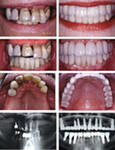

Имплантаты костные-Импланта?ты (также ошибочно импла?нты, имплантанты ((англ. implant - вживлённая (пересаженная) ткань) — класс изделий медицинского назначения